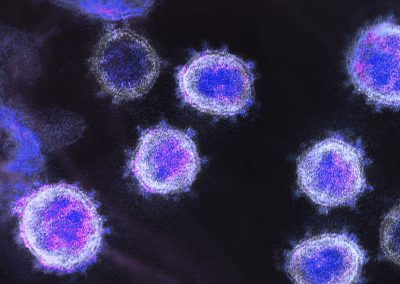

¿Qué son las células madre?

Las células madre, también conocidas como células troncales, son el origen de todos los tejidos que conforman el cuerpo humano, y se caracterizan del resto de las células por su capacidad de cumplir dos funciones únicas:

- Autorrenovación. Estas células se pueden dividir para fabricar copias idénticas de sí mismas de forma indefinida, es decir, se puede autocopiar la cantidad de veces que el organismo así lo requiera.

- Diferenciación. Las células madre se pueden transformar en cualquier tipo de célula especializada, como células de la piel, fibras musculares, células del corazón; incluso pueden transmutar como neuronas.